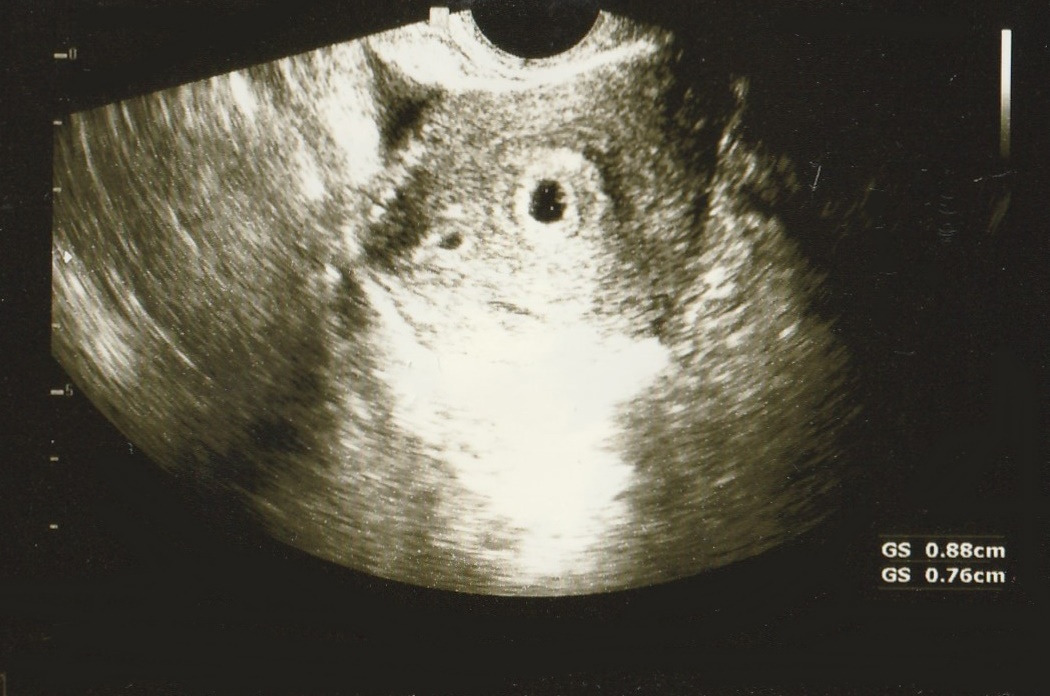

"아기집이 두 개네요 ~ "

"네??"

한새연우 초음파사진1.jpg 오른쪽 큰아기 집이 첫째, 왼쪽의 작은 아기집이 둘째입니다...^^